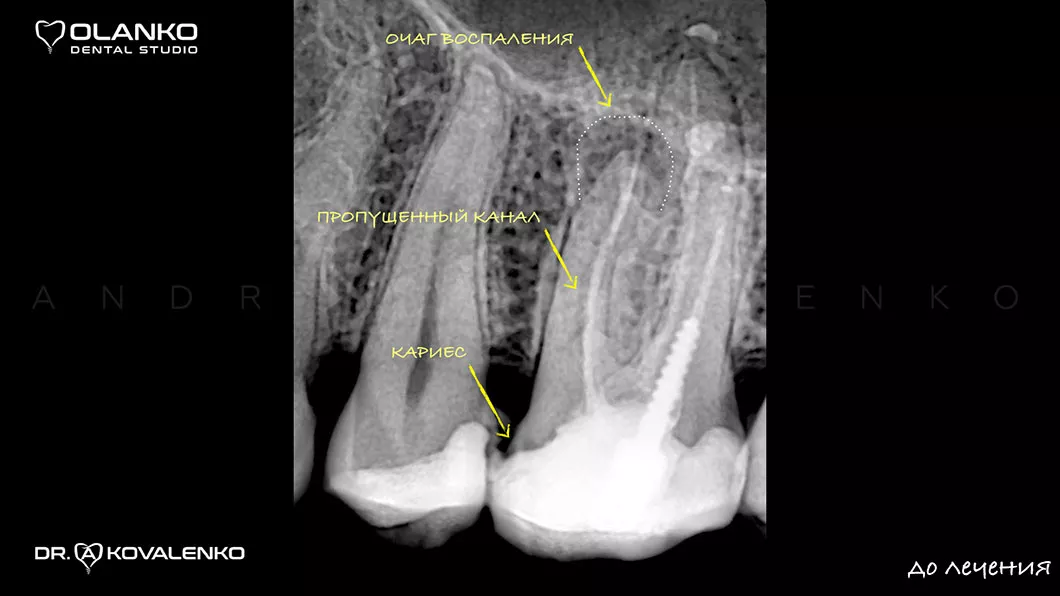

до

На сьогоднішній день, лікування зубів з використанням мікроскопу — це золотий стандарт світової стоматологічної практики. Складна система кореневих каналів має дуже малий діаметр та індивідуальну анатомію, тому лікар, який працює без збільшення, майже на дотик, не може якісно їх пролікувати.

Важливою перевагою Olanko dental studio (Оланко) м. Бровари є виконання всіх етапів лікування кореневих каналів тільки під контролем операційного дентального мікроскопу!

Ми маємо величезний клінічний досвід лікування зубів зі складною анатомією (викривленими, склерозованими каналами), а також повторного переліковування каналів з кістою, гранульомами, зламаними інструментами, з подальшими відмінними результатами загоєння хронічних запалень.